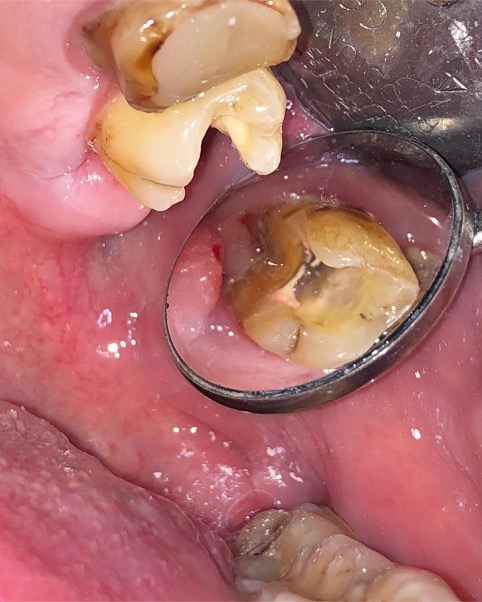

Un trattamento endodontico consiste nel salvare un dente compromesso da carie, traumi o fratture rimuovendone polpa e nervi infetti/infiammati responsabili di dolore, ascessi, cisti e granulomi.

Un adeguata endondonzia serve per salvare quei denti che altrimenti sarebbero destinati ad essere estratti. Quando un dente viene devitalizzato viene privato della sua irrorazione sanguigna e del nutrimento, rendendo la sua struttura più “vetrosa” quindi più fragile e soggetta a fratture. Per questo motivo è consigliabile nella maggior parte dei casi capsulare i denti una volta che hanno perso la loro vitalità.